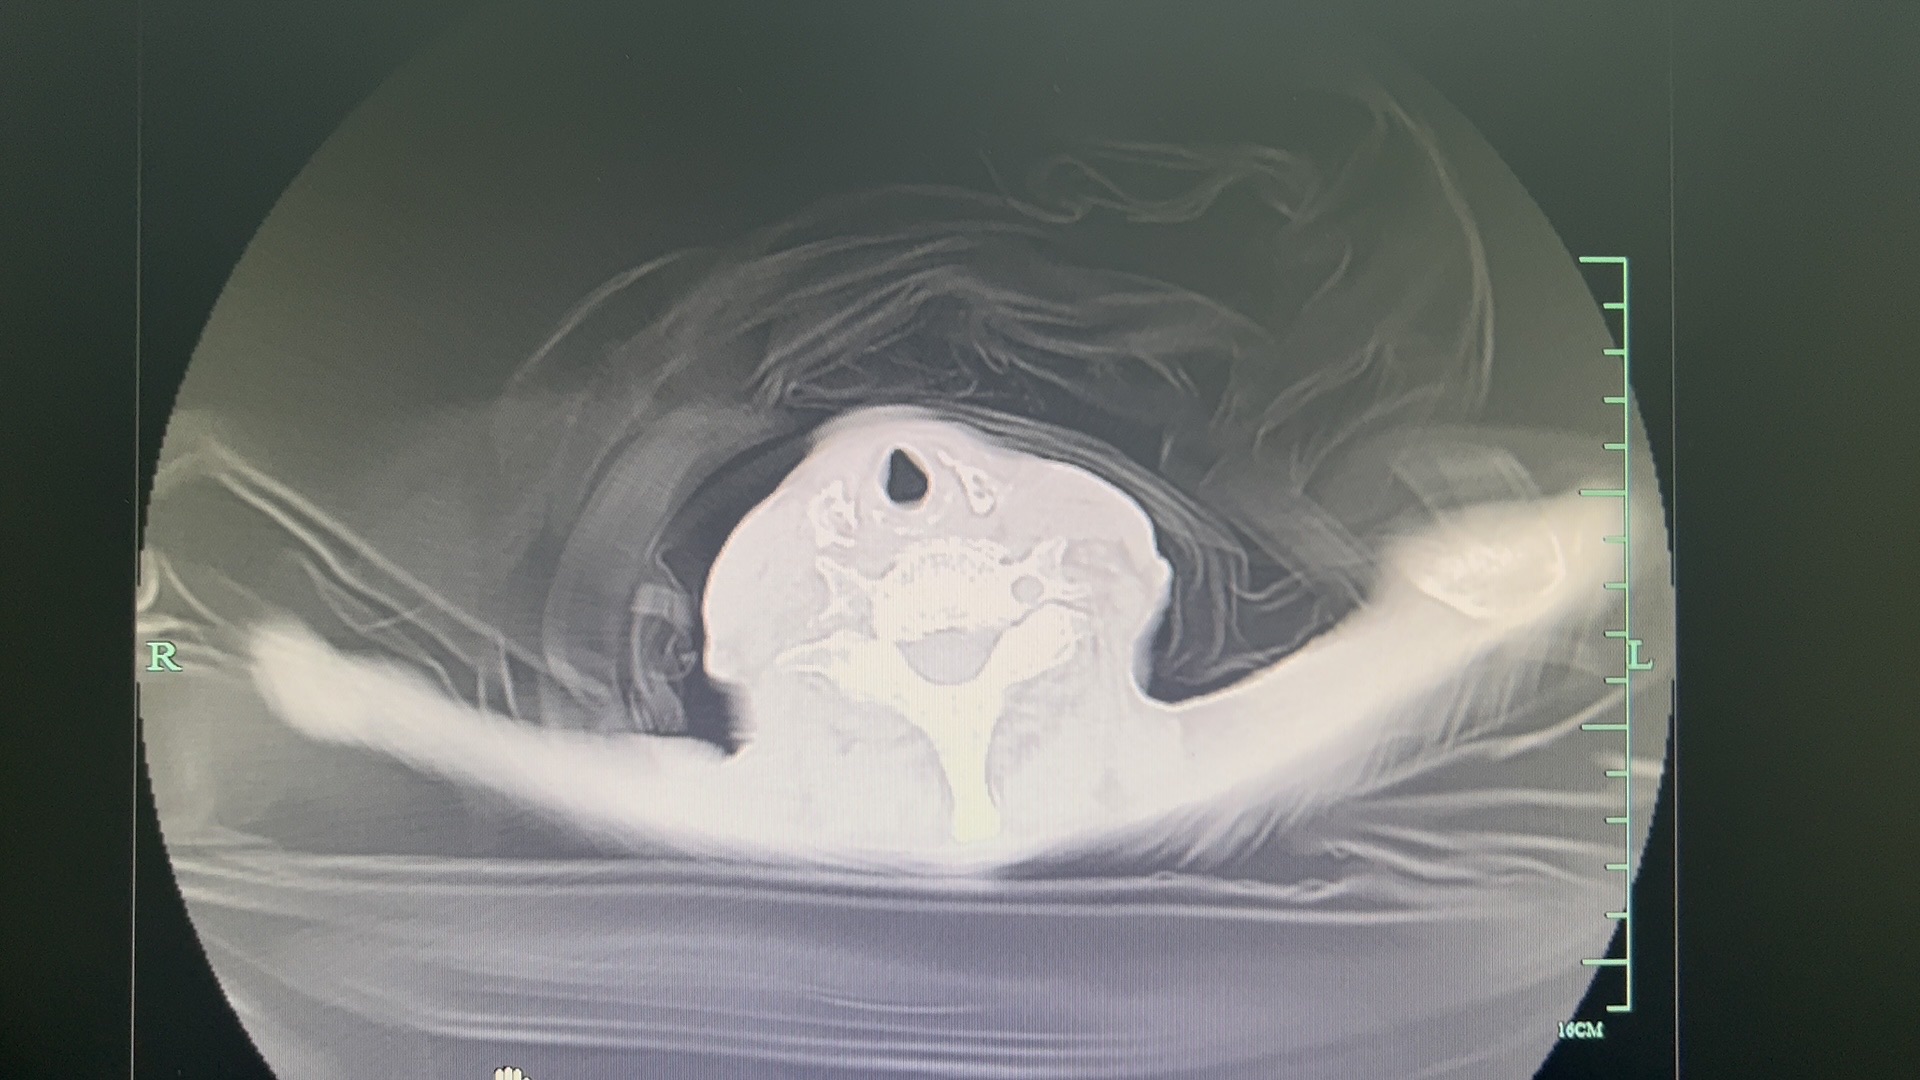

李梦杰huxi 达人已点赞患者,女,90岁,此次以食物减退伴乏力3天,加重伴气促1入院。既往否认任何疾病史。入院时神志淡漠,精神差,体温好38度,血压 90/40mmHg 呼吸 24次/分 脉搏 86次/分。两肺呼吸音粗,未闻及干湿罗音。考虑肺炎,给予莫西沙星联合头孢派通舒巴坦抗感染治疗。